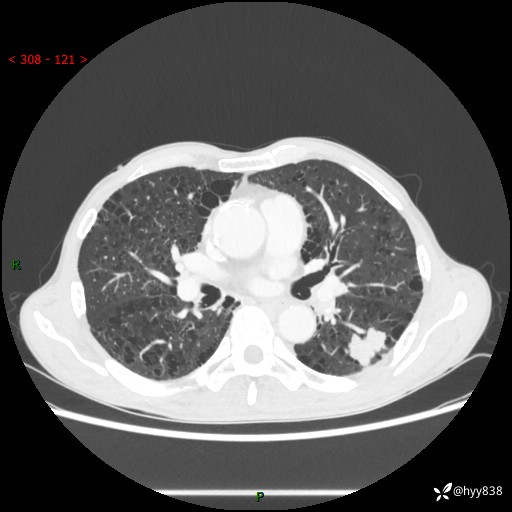

73岁/男,发现肺占位1月余。肺气肿背景,是否恶性倾向---结果公布~

现病史:患者于1月余前无明显诱因出现背部疼痛不适,无明显咳嗽、咳痰、胸闷、咯血、发热等不适,后于2024.5.3至当地市人民医院行胸部CT示:左肺下叶结块,大小约2.2cm*2.6cm,双肺多发小结节,双肺感染性病变,部分纤维增值灶,慢支并双肺局限性肺气肿,肺大泡,纵隔淋巴结增大并部分钙化,冠脉区及大血管壁钙化,双侧胸膜局限性增厚;后口服莫西沙星2周。2024.6.12复查胸部CT示:左肺下叶结块影形态较前饱满,较大截面范围约2.8cm*2.3cm,边缘可见细短毛刺及分叶,性质待查。现患者为求进一步诊治来我院,门诊以“肺占位”收入我科。 起病来,患者精神、食欲、睡眠尚可,大小便正常,体力体重轻微下降。

胸部CT平扫+增强

各期CT值:48hu 100hu 78hu